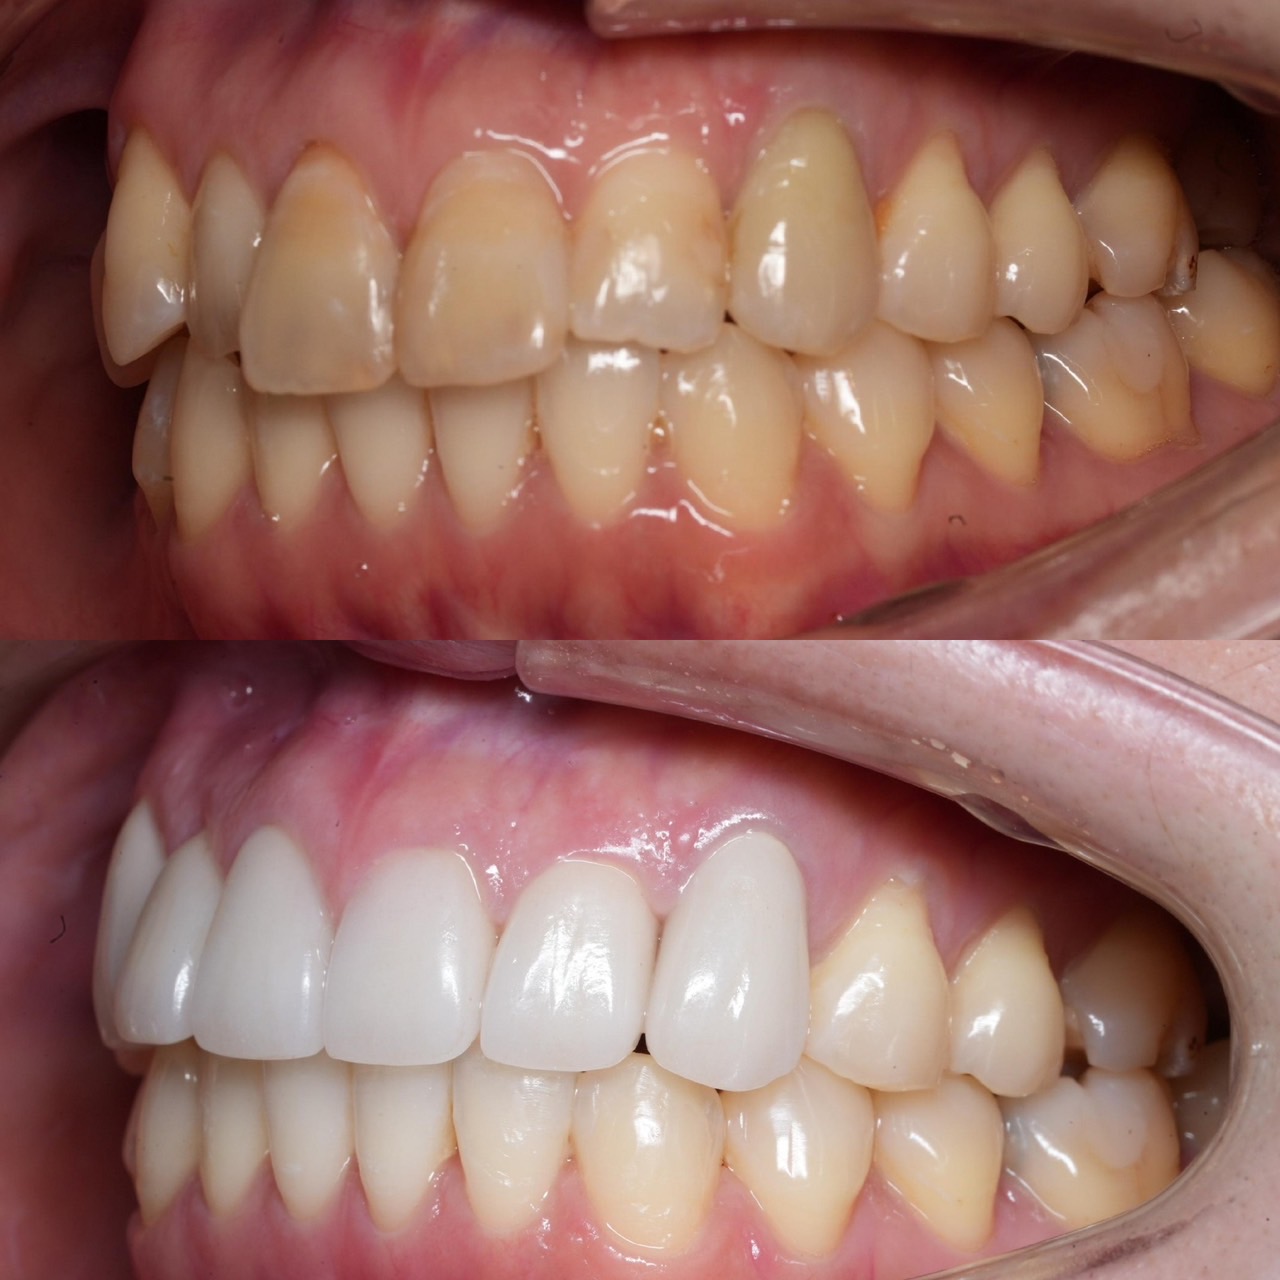

Case022 – インプラント

広島からの患者様です。

前歯を綺麗にしたい。インプラントをしたい。

という主訴で東京の歯医者をいろいろ調べて当院を選んでくださいました。

毎回、遠い中しっかり通ってくださり、選んで頂けた嬉しさと、その気持ちに応えたいという想いで診療させて頂きました。

前歯はご希望のお色でラミネートベニアでは出せない透明感のあるセラミックに上下左側7はインプラントをさせて頂きました。

左上は破折で温存不可。

骨も少なかったので、サイナスリフトも行い計五回の来院で被せ物を入れさせて頂きました。

左下は前回のクリニックでの埋入位置が深すぎて食べカスも毎回詰まる、セルフメンテナンスではら汚れも取れない。インプラント周囲炎にもなっていたので、一度前のインプラントを除去し、そこから新しくインプラントを埋入し、診療させて頂きました。